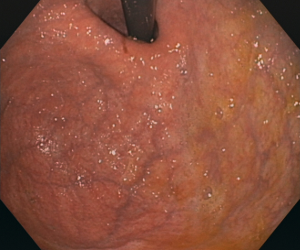

Conventional white-light endoscopy has a relatively low sensitivity, low specificity and high inter-observer variability for the diagnosis of atrophic gastritis. Thus, it is thought to be insufficient to reliably diagnose it. Our goal is to improve endoscopic accuracy for the diagnosis of atrophic gastritis using deep learning.

Our convolutional neural network was trained to analyze endoscopic images from the proximal stomach, achieving an accuracy of 92.9% and performing significantly better than the combined results of 6 independent endoscopists. With this web tool we want to provide wide access to this software. It allows you to upload your own endoscopic images for analysis, and provides an indicative diagnosis.